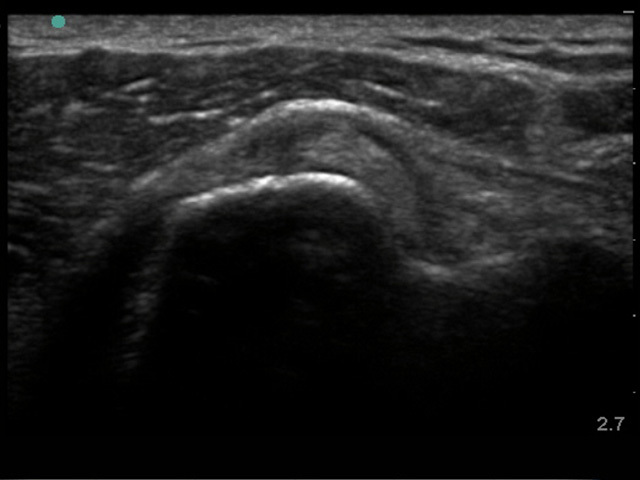

Shoulder Bicep Subluxation 2 Image